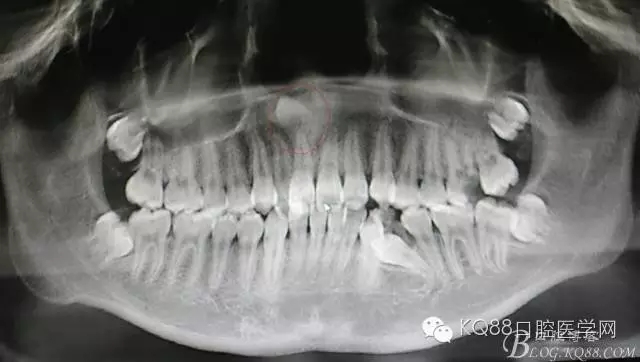

圖1.CBCT全景片重建檢查:11根尖區(qū)上方有一倒置多生牙

患者、女、13歲,主訴:上前牙擁擠,要求矯正。專科檢查:21腭側錯位萌出,CBCT檢查:11根尖區(qū)有一倒置多生牙,多生牙會影響正畸治療,建議外科手術拔除多生牙?;颊咄庵委煼桨?、簽知情同意書。